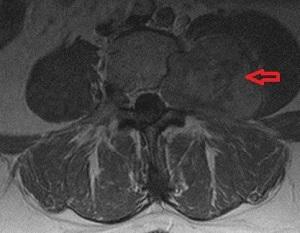

Невринома спинного мозга представляет собой доброкачественную опухоль, возникающую из нервных корешков позвоночника и формирующуюся из шванновских клеток.

Опухоль может расти на протяжении длительного времени, достигая размеров до 2,5 см. Наиболее подвержены поражению шейно-грудной отдел позвоночника, в то время как поясничный отдел затрагивается реже.